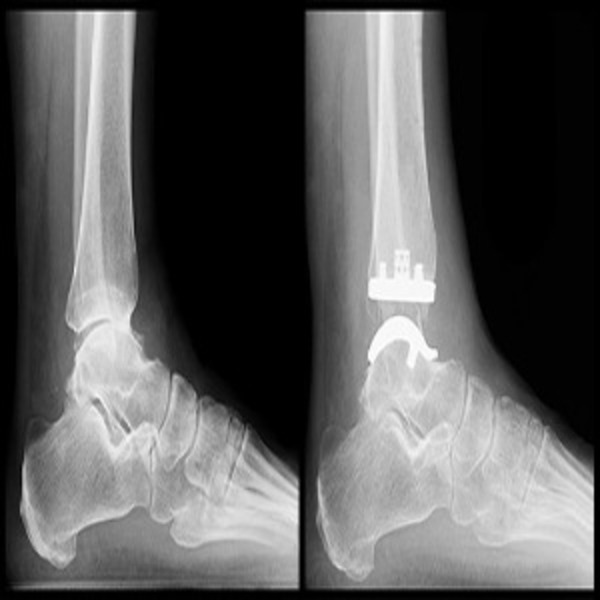

Ankle Instability Doctor in Nagpur – Restore Confidence in Your Movement Tired of frequent ankle sprains or that uneasy wobble while walking? The ankle instability doctor in Nagpur at Suyog Hospital focuses on strengthening your ankle joint and stabilizing its function. Chronic instability not only increases fall risk but can lead to long-term joint damage if left untreated. We assess your history of injuries, perform a detailed physical exam, and create a plan that may involve physical therapy, bracing, or surgical repair of damaged ligaments. Our holistic approach aims to rebuild confidence in every step you take. Don’t let weak ankles slow you down. Consult the trusted ankle instability specialist at Suyog Hospital in Nagpur and regain strength, support, and stability for active living.